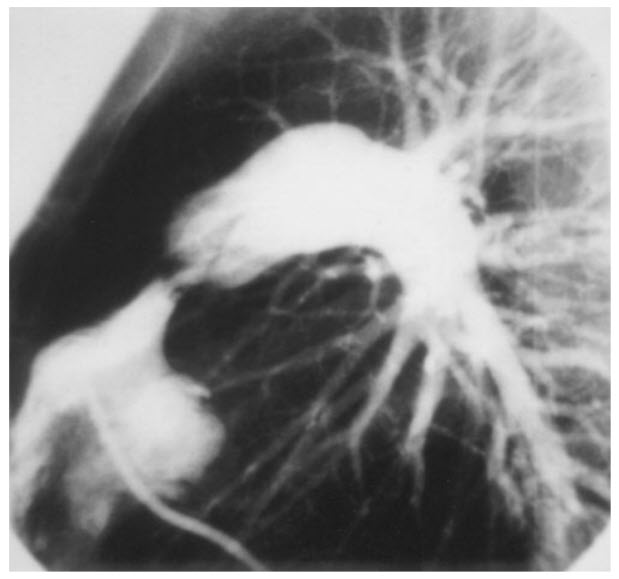

Match the following cardiac catheterization still-frame slide to it's respective diagnosis.

A. Coarctation of the aorta

B. Patent ductus arteriosus (PDA)

C. Hypertrophic cardiomyopathy

D. Pulmonic stenosis

E. Ventricular Septal Defect (VSD)